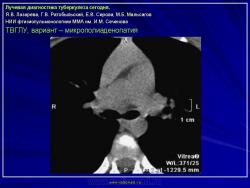

Лучевая диагностика туберкулеза сегодня

Я.В. Лазарева, Г.В. Ратобыльский, Е.В. Серова, М.Б. Мальсагов

НИИ фтизиопульмонологиии ММА им. И.М. Сеченова